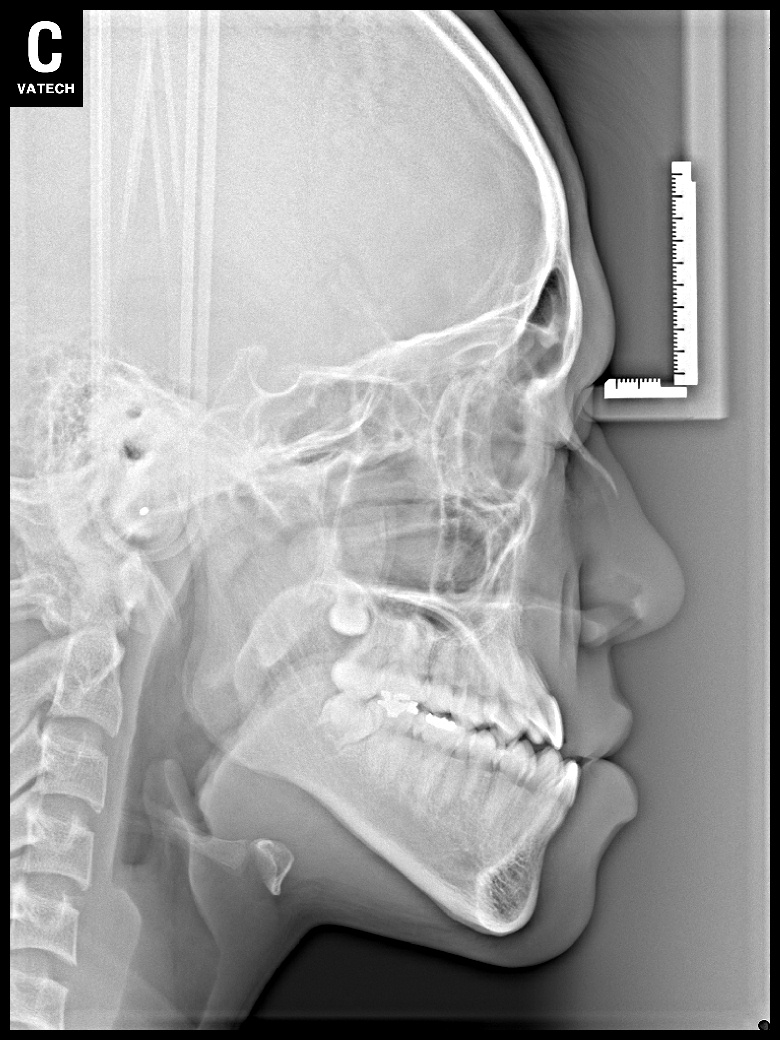

치료 전 사진입니다.